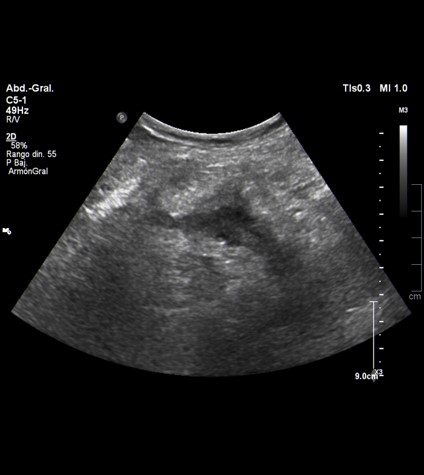

La prueba de elección es la ecografía puesto que es el estudio más indicado para la visualización de órganos y partes blandas en el abdomen. No tiene radiación ionizante, es una prueba no invasiva y tiene una gran disponibilidad.

HALLAZGOS: Engrosamiento de paredes del ciego en FID